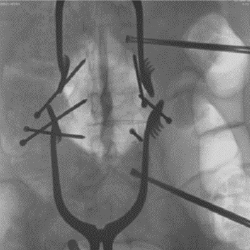

DSA

The DSA and roadmap functions make it suitable for intravascular procedures.